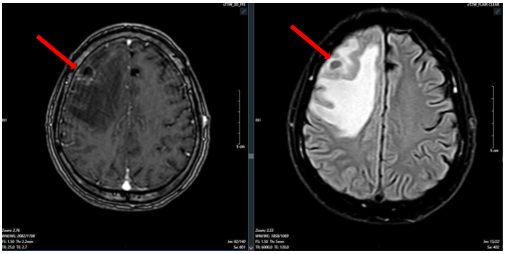

Bệnh nhân được chụp cộng hưởng từ sọ não, phát hiện khối u vùng trán phải, kích thước 17 x 20 mm gây phù não rộng xung quanh theo dõi tổn thương thứ phát

Hình 1

. Hình ảnh cộng hưởng từ sọ não ngày 25 tháng 03 năm 2025 (hình bên trái: xung T1; hình bên phải: xung T2) cho thấy khối u não vùng trán phải (mũi tên).